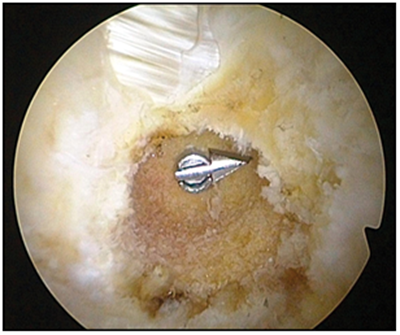

To perform the Femoral hole, we place in the PM the femoral guide on a anterograde way, by the PM we put the Over the Top, special for the performance, through the antero-medial portal and then we pass the bottom hole rod, that will serve as a guide for the cannulated wick of 9 or 10 mm. We do it this way and not with retrograde wick. In this surgical moment, there are two very important keys to make this hole; one is to make them as large as possible (about 40 mm) to prevent the neo-ligament not to enter completely and that it remains lax, meaning that it should enter completely to the tunnel for an excellent ligamentacion, the neoligament has to be in contact with the tunnel and fixating the end tibia with 70 degrees of flexing on the anterior drawer. To repair the femoral, in which we still have placed the guide pin, we pass through it a nitinol rod, which is recovered by the PM and then we put a Fiber wire (Arthrex), we traction the guide pin, bringing back the nitinol rod we proceed to place the graft. This is accomplished with the next maneuver, taking the fiber wire, that we left out of the anterio-medial portal, and tie it to the Loop of Retro Button, when we traction distally the end it should enter to the tibial hole and be fixed to the outer tibial cortex. In one only motion, making this easier and shorten the surgical time (Figure 7).

Figure 7 We watch how pass allograft with the fiber wire through the hole tibial